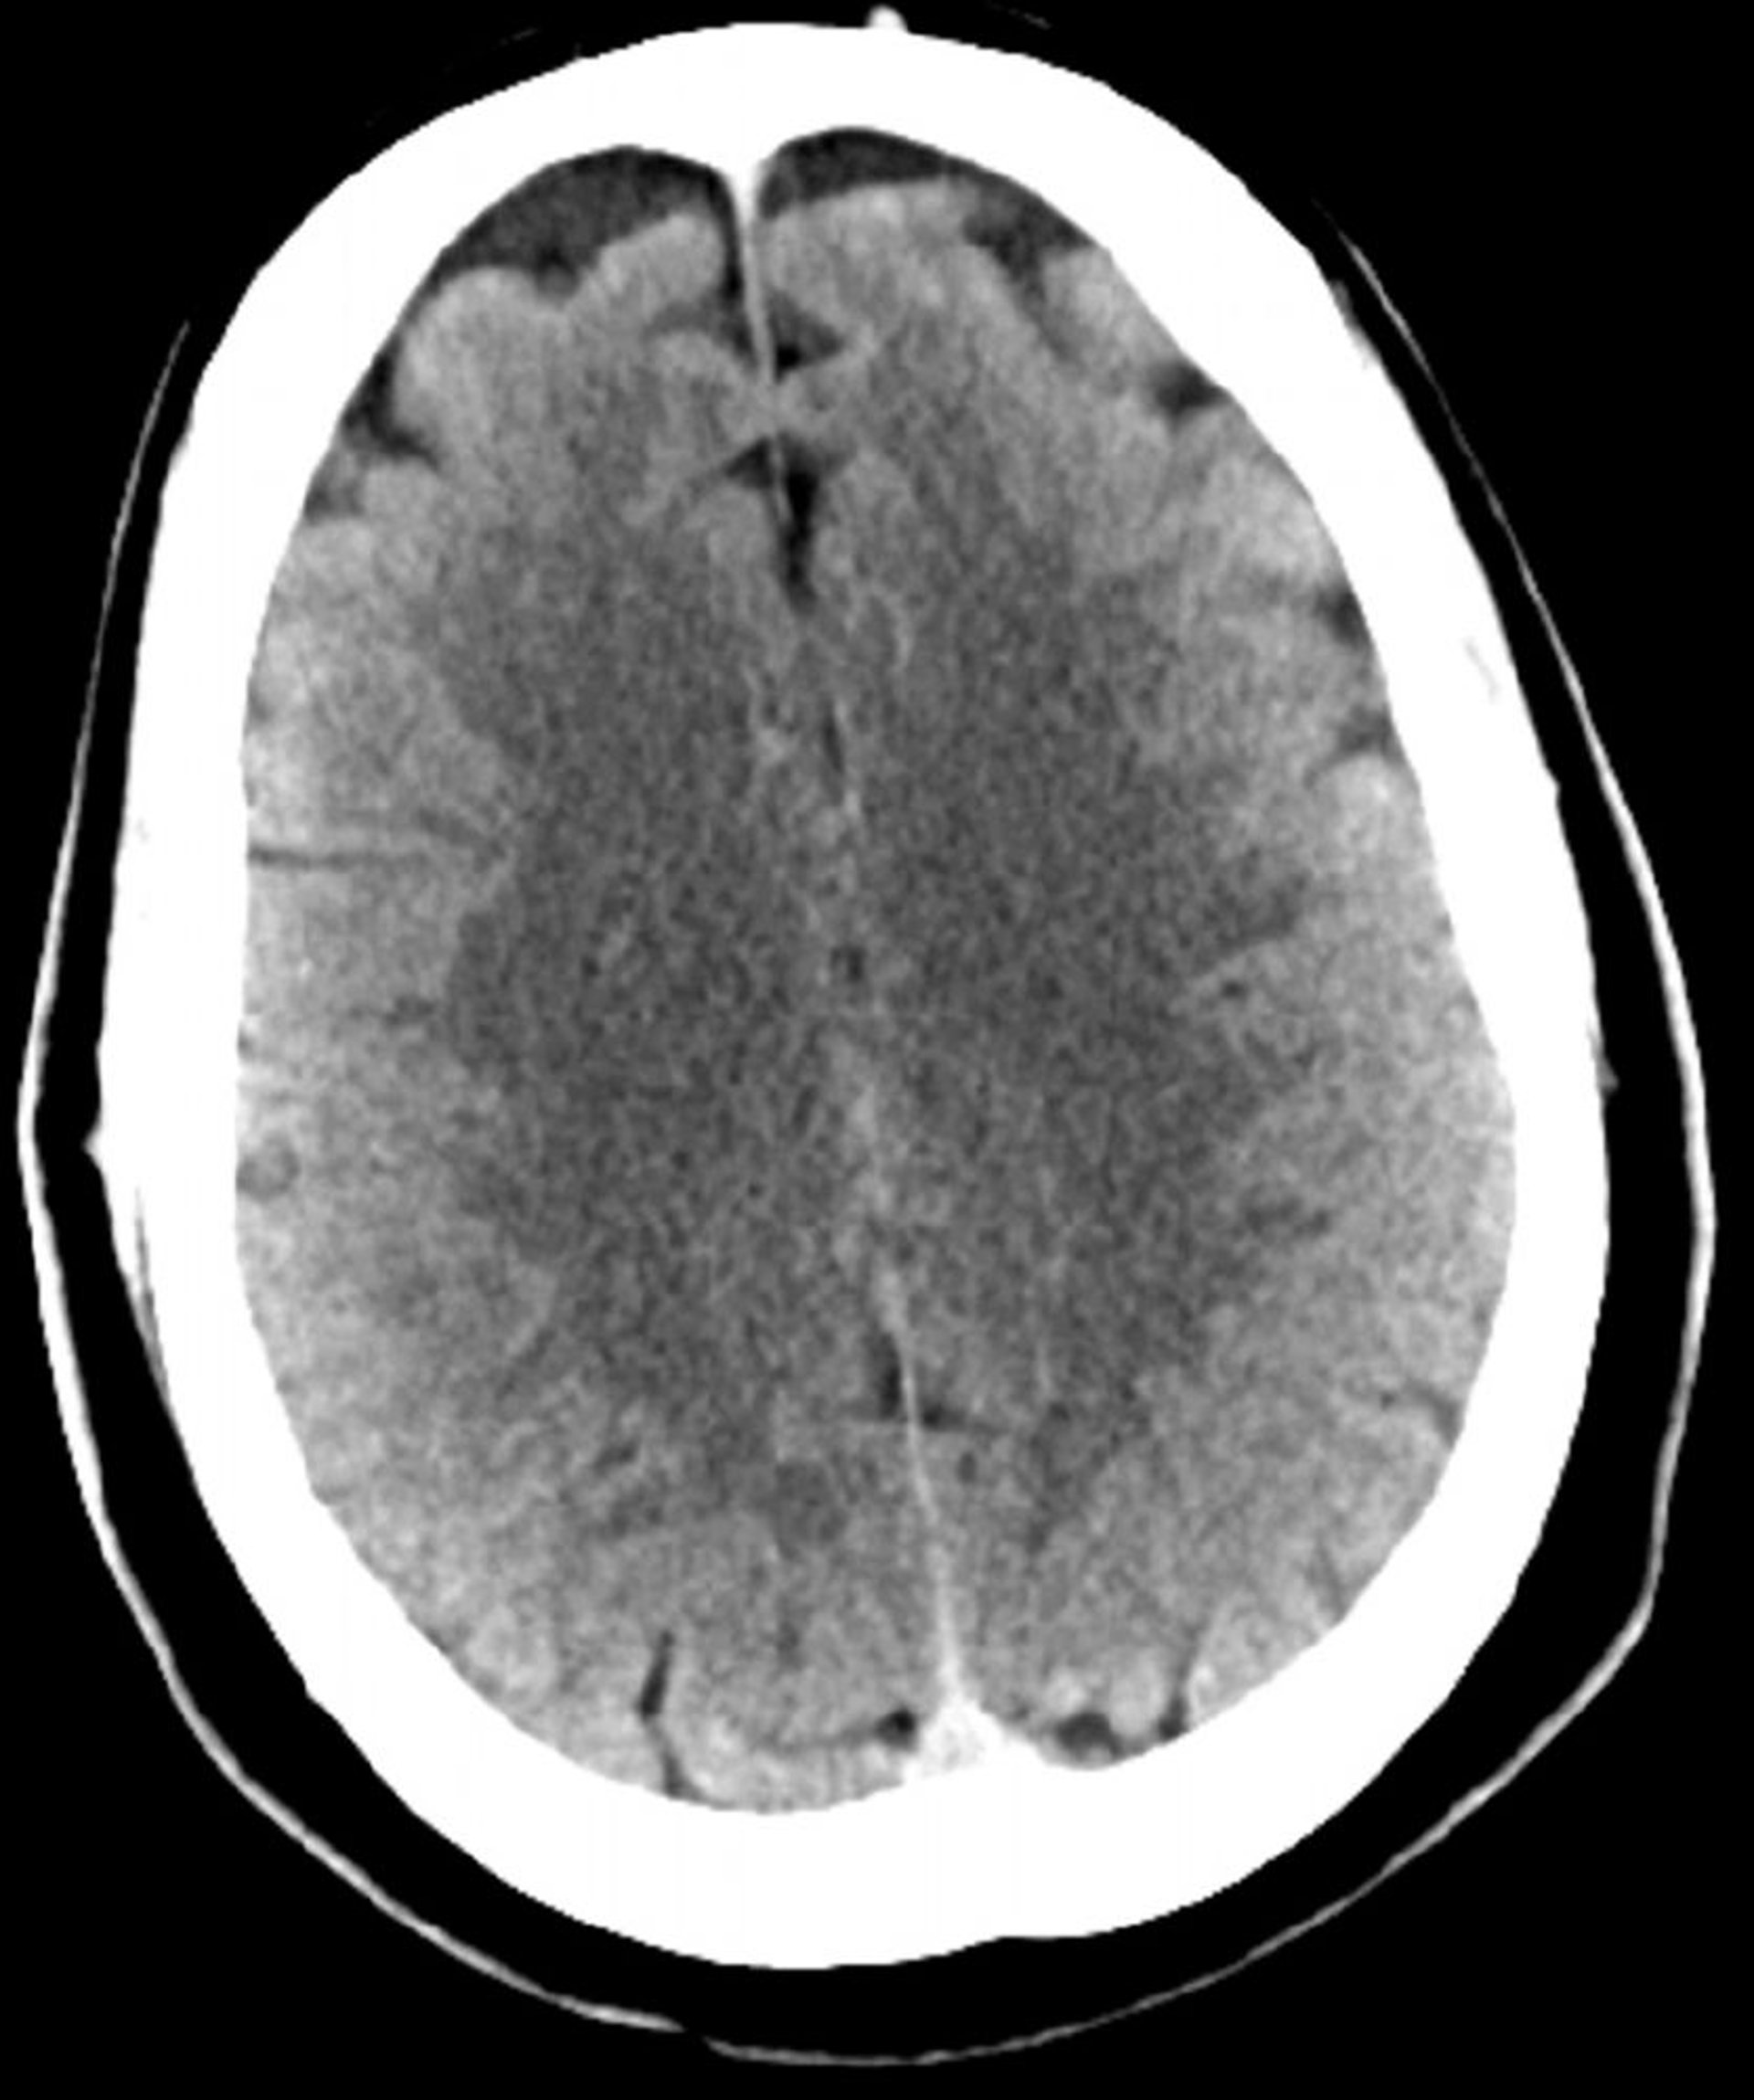

Tomodensitométrie normale de la tête (adulte 30 ans) – Diapositive 2

Cette image est une TDM normale de la tête d'un jeune adulte âgé de 30 ans. Il n'y a pas de liquide intra- ou extra-axial ou d'hémorragie. La différenciation gris-blanc est préservée. La forme des sillons est normale.